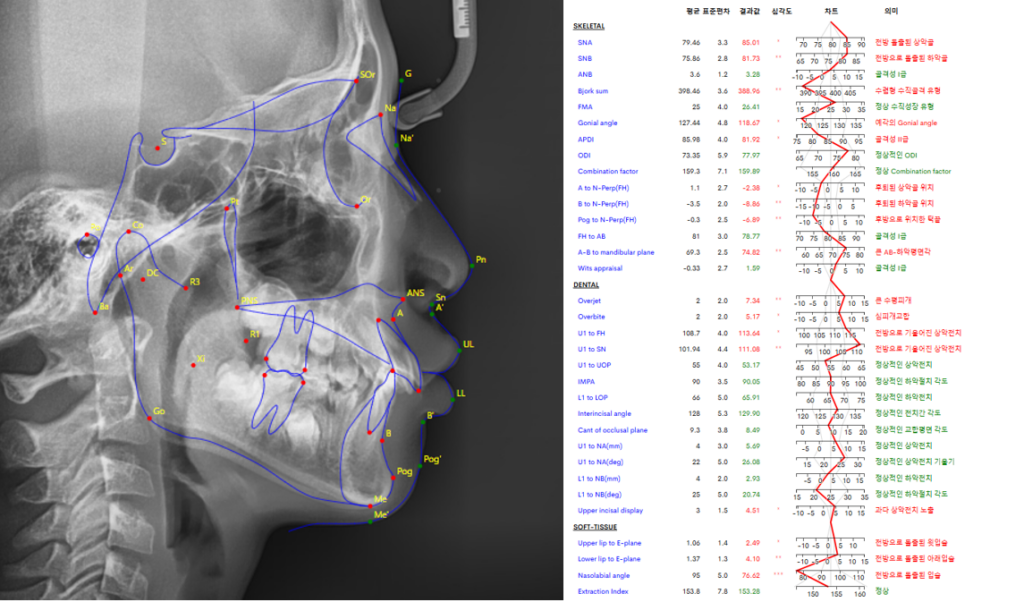

중랑구 교정치과 에서는 클린체크 시뮬레이션을 통해 앞으로 나올 영구치 위치를 예상하고 그에 맞춰 악궁을 확장하거나 치아 배열을 유도합니다.